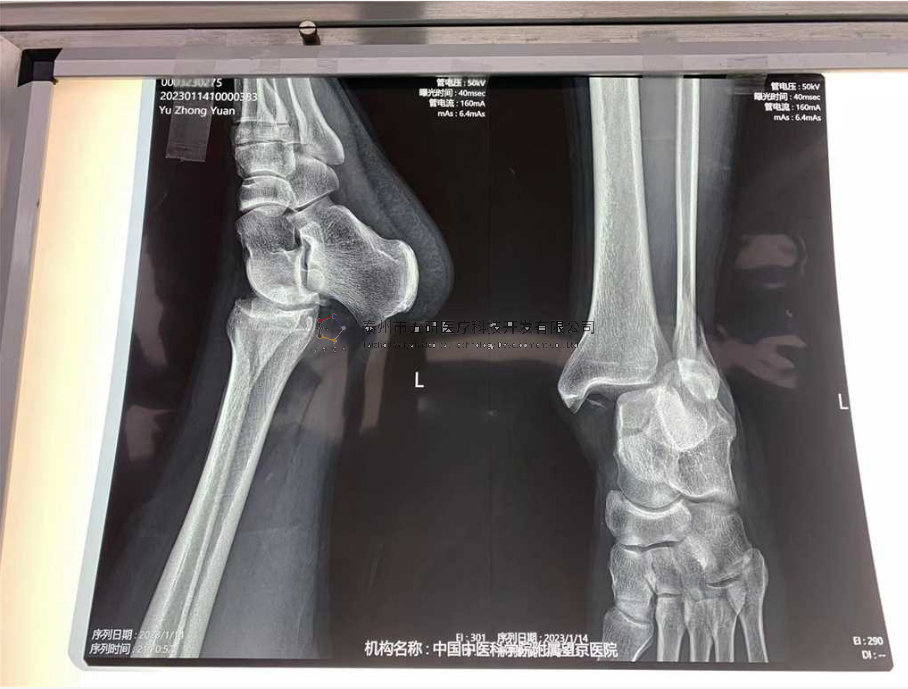

本病例踝關(guān)節(jié)骨折。手術(shù)名稱:左踝關(guān)節(jié)骨折外固定支架手術(shù)

【治療前影像】

4.png

5.png